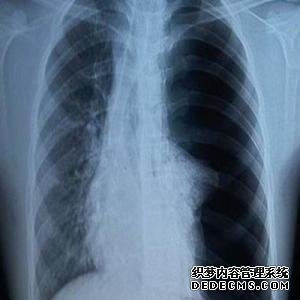

什么是咳嗽,胸痛,拍摄,肺部疾病?

国家分析:你好,你目前的描述,但你的父亲有权更正肺部感染,因为肺癌不能排除,我认为有胸膜炎和严重疾病的可能性。

建议:1.有一种方法可以先进行CT扫描以改善胸部,并在进行抗感染治疗后首先检查胸部CT扫描,但先进行为佳

2,胸部超声检查主要可以进行以看胸膜的情况

3,控制血液常规,红细胞沉降率,肿瘤标志物。

4.如果排除了肿瘤,则可以是积极的抗感染治疗。

5,需要戒烟

在拍摄过程中被问到时,您是否发现肺部有严重阴影?